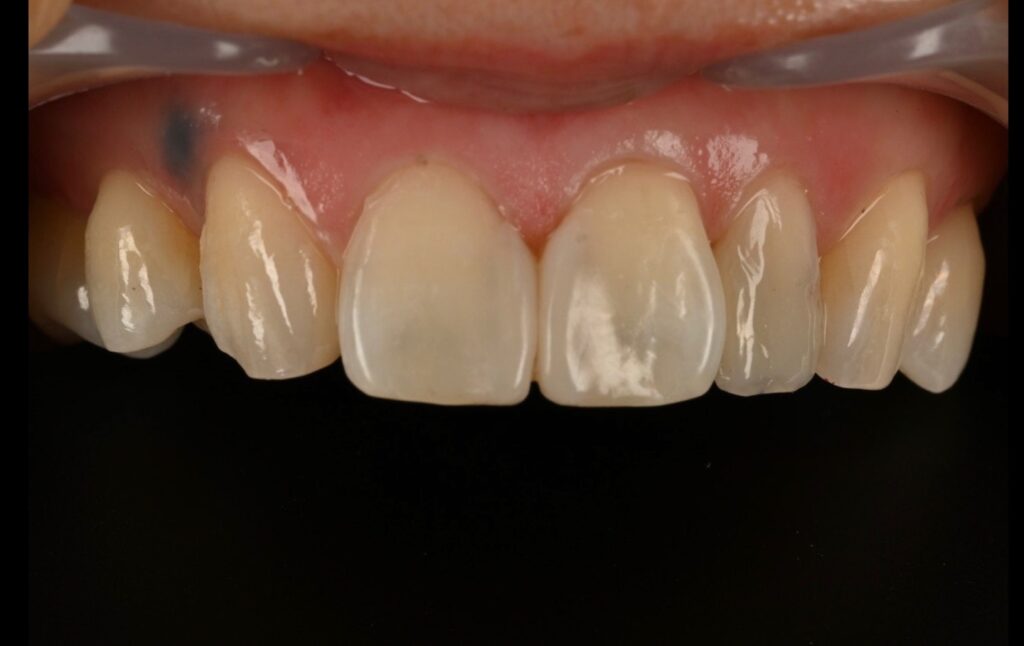

1차 피니싱과 폴리싱 완료후 모습입니다

완전히 자연스러운 모습입니다만

치경부 즉 치아의 경계 부위의 형태가 조금 걸립니다

하지만 이 부분은 러버댐이 잇몸을 눌러서 생긴 현상이기에

2주후 추가 피니싱을 하기로 하였습니다

내원당일의 모습

레진 치아성형은 치료 당일은

1.색상이 발현되지 않아서 달라보일 수 있습니다

2.잇몸이 차오르는 모습을 봐야 합니다

-2주 후 기다려서 추후 경과를 봅니다-

2주후 모습입니다

색상과 그리고 잇몸이 차오른걸 볼 수 있습니다

최종 모습입니다

혹시 이상하다고 생각하시는 분들이 있겠지만

측절치 즉 왜소치의 레진성형도 완성이 되어서

치료 후의 모습이라고 보시면 됩니다